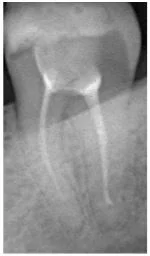

Давайте сравним снимки зубов, сделанные при помощи визиографа (слева), и при помощи компьютерной томографии (справа).

Как говорится, ощутите разницу. КТ - гораздо более точная и своевременная диагностика.